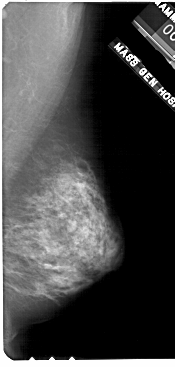

A_1709_1.RIGHT_CC

RIGHT_CC LINES 4411 PIXELS_PER_LINE 2311 BITS_PER_PIXEL 12 RESOLUTION 43.5 NON_OVERLAY